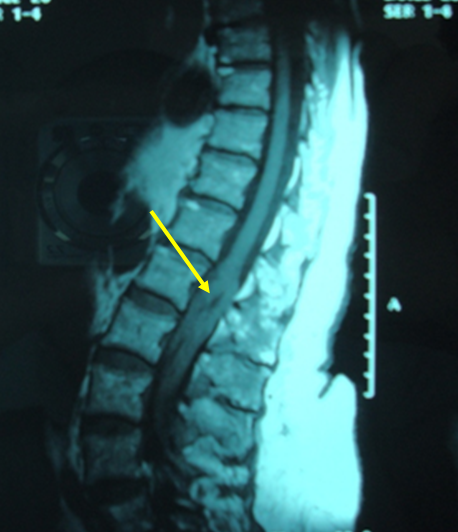

Le lymphome épidural primitif est une tumeur rare qui représente moins de 10 % des tumeurs épidurales et moins de 1% des lymphomes non hodgkiniens. Le tableau clinique est souvent bruyant associant des rachialgies initiales puis des signes neurologiques déficitaires sensitifs (67 % des cas) ou moteurs (90 %), et exceptionnellement un syndrome de la queue de cheval. Nous rapportons l’observation d’une femme âgée de 82ans qui consulte devant une faiblesse des deux membres inférieurs et des troubles sphinctériens à type d’incontinence urinaire et de paresthésies de la zone périnéale (anovulaire). L’examen physique trouve une patiente en bon état général, une paraparésie avec hypoesthésie des deux membres inférieurs avec un niveau sensitif L4, une anesthésie en selle et des troubles de la sensibilité profonde. Il n’y a pas de syndrome tumoral. L’IRM médullaire a révélé une lésion tissulaire extra-durale en regard de L2 L3 L4 en iso signal en T1 et en hyper signal en T2. Une laminectomie au niveau de L2 L3 L4 réalisée a conclu à un lymphome non-hodgkinien à grandes cellules de phénotype B. Un bilan d’extension de la maladie pratiquée a montré une atteinte méningée. Le diagnostic de lymphome épidural primitif avec localisation méningée a été retenu. La patiente a reçu 4 cures de Chimiothérapie (MINI CEOP) selon le protocole LNH08 groupe 5 avec une excellente réponse clinique et radiologique. Le pronostic du lymphome épidural primitif est relativement bon à cinq ans avec une survie globale de 70 %une survie sans maladie de 50 %.